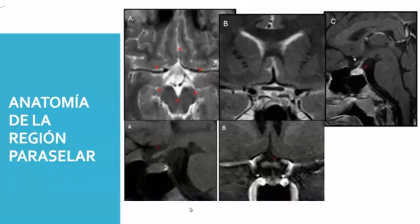

Tema: Patologías region selar

Dictado por: Dr. Bedrán